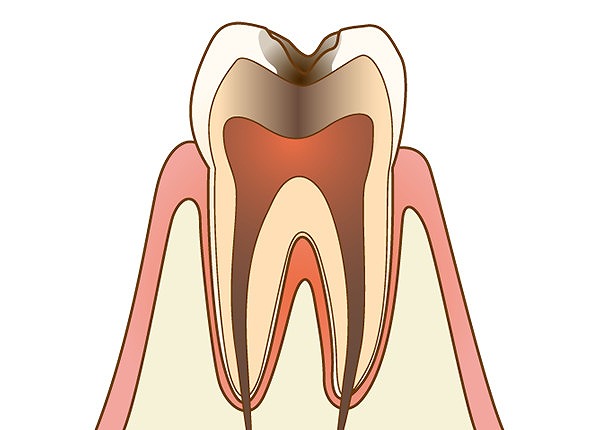

C3:神経に達したむし歯

象牙質の内側にあって、神経や血管が通っている歯髄にまでむし歯が達しています。何もしなくてもズキズキとした強い痛みがあります。

象牙質の内側にあって、神経や血管が通っている歯髄にまでむし歯が達しています。何もしなくてもズキズキとした強い痛みがあります。

精密な根管治療で歯髄から神経を取り除き、薬剤を充填して密封した後に被せ物で補って治療します。

C4:歯根に達したむし歯

歯を支える歯槽骨に接する歯根にまでむし歯菌に侵されています。歯ぐきの上に現れている歯冠部分はかなりの部分が溶けてなくなっています。歯髄にある神経が死んでしまっているため、痛みが治まっていることもありますが、歯根部分が膿んでくると強い痛みが現れます。

歯を支える歯槽骨に接する歯根にまでむし歯菌に侵されています。歯ぐきの上に現れている歯冠部分はかなりの部分が溶けてなくなっています。歯髄にある神経が死んでしまっているため、痛みが治まっていることもありますが、歯根部分が膿んでくると強い痛みが現れます。

抜歯しなければいけないケースが多くなり、入れ歯やインプラント、ブリッジなどの治療で補う必要があります。